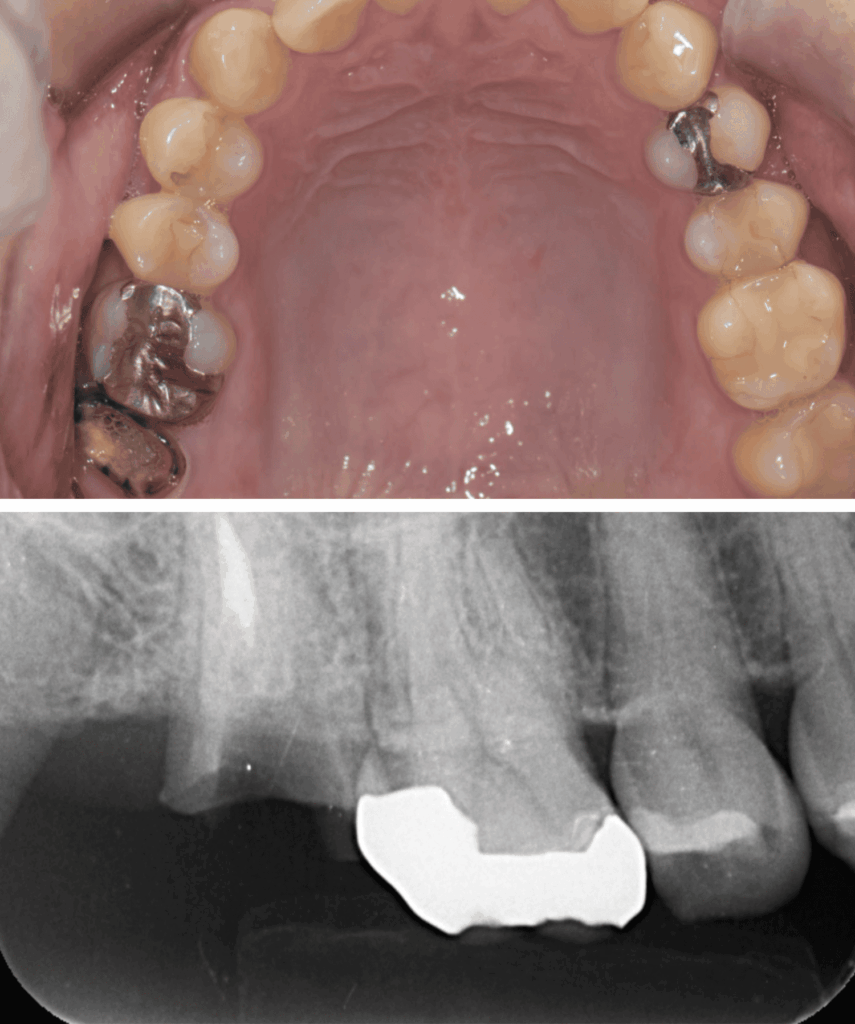

歯と歯の間のう蝕の為肉眼では分かりにくく、気づいた時には歯髄に近接し、保険治療では抜髄(神経を除くこと)になってしまうケースが多い。そのため処置前に、十分な精査と、患者さんが神経を残したいという希望の有無をしっかり相談・説明することが重要と考えています。

| 診断 | ①右上7根尖性歯周炎 ②重度う蝕 ③左上7歯髄に近接するステージ3のう蝕 |

| 処置内容 (または主訴) | ①マイクロスコープによる根管治療 ②マイクロスコープによるう蝕除去およびセラミック修復 ③MTAを用いたマイクロスコープによる歯髄温存療法からセレック修復 |